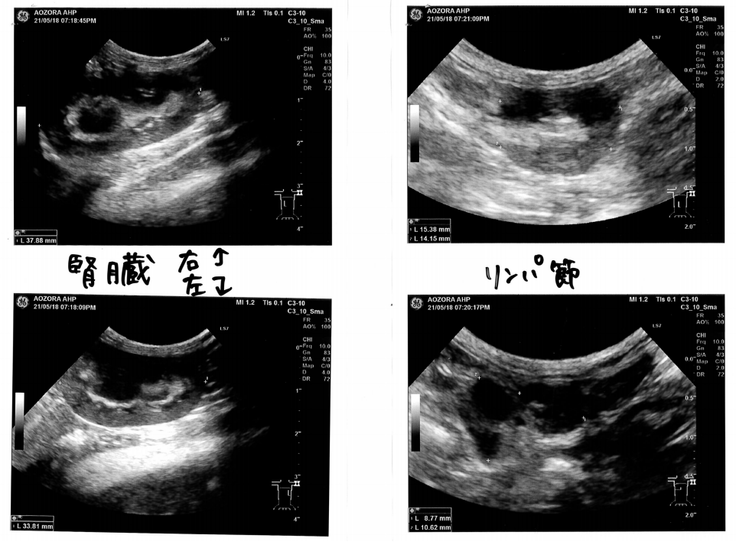

5月11日にA動物病院に連れていき血液検査から5月16日に猫伝染性腹膜炎(FIP)のドライ型だろうという検査結果を受けました。念のため別の動物病院(あおぞら動物病院)でも5月18日診察に伺い、下記検査結果の「ALB(アルブミン)/GLB(ブロブリン)比が目安となる0.45未満の0.38で猫伝染性腹膜炎(FIP)」と診断されました。

リンパ腺も約3倍に腫れておりました。